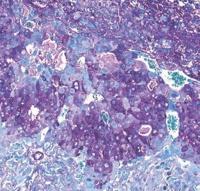

Mice with Bifidobacterium breve in their gut lost fewer of their pregnancies. (Jorge Lopez-Tello/ Cambridge University via SWNS)

The mice with Bifidobacterium breve in their gut lost fewer of their pregnancies.

Pregnant mice without Bifidobacterium breve in their gut had a higher rate of complications, including fetal growth restriction and fetal low blood sugar, and increased fetal loss.